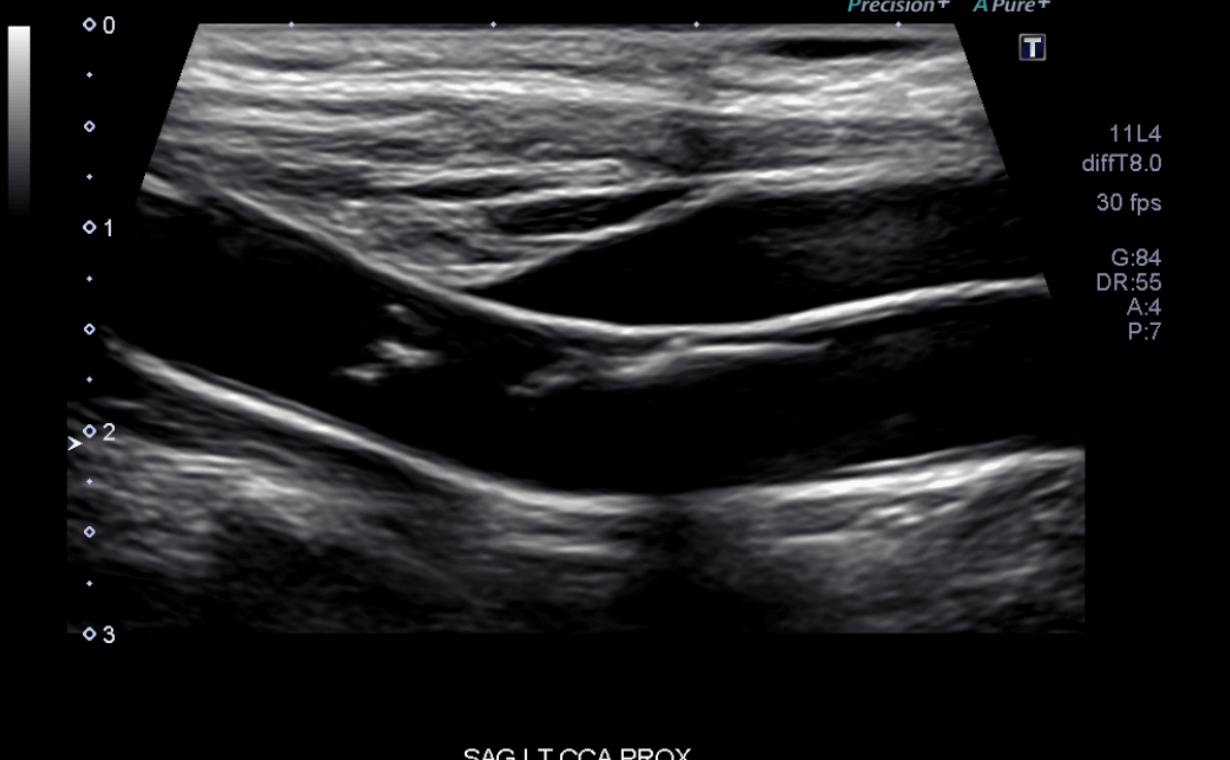

Carotid Artery Images

These images display detailed test results and readings from carotid artery scans, offering critical insights into vascular health. The data includes ultrasound imaging, blood flow velocity measurements, and plaque assessments, helping to evaluate the risk of stroke and cardiovascular conditions. These readings assist medical professionals in diagnosing potential blockages, monitoring arterial health, and guiding treatment plans for optimal patient care.